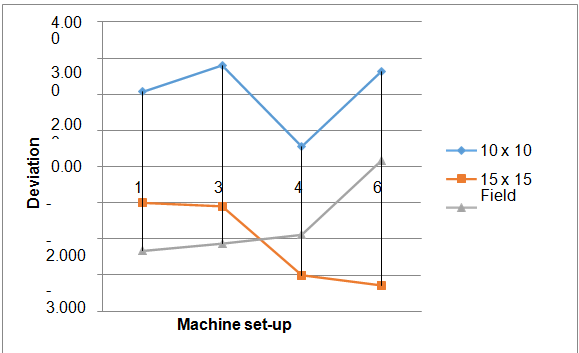

After calculating wedge angles we determine the deviations between calculated angles and machine set-up angles by subtracting calculated angles from machine set-up angles in degrees then finally calculated the percent deviation. The Figure 2 shows the percent deviation between machine set-up angles and calculated angles for 6 MV energy. This shows that the deviation is independent of machine set-up angles and field sizes the deviation in this case within 4 %. The Figure 3 shows the percent deviation between machine set-up angles and calculated angles for 15 MV energy. This shows that the deviation is independent of machine set-up angles and field sizes, the deviation in this case within 3 %. The variation or deviation in 15 MV is lesser than 6 MV it is may be due to beam hardening effect in 6 MV, beam hardening is the effect when radiations passes through from metal low energy captured in metal. The previously study was done on PRIMUS3008 linear accelerator Siemens and the deviation between calculated and machine set-up angle is found to be within 1%.16 The recent study regarding the wedge angle confirmation for Elekta for 15° 15 cm2 field size is given in Table 3.17 Our study shows the deviations from original value within 3 % ,which is acceptable this variation increases in higher fields due to the electron contamination with x-rays beam ,deviation also increases with wedge angle as thickness increases energy decreases. As far as the effect of energy beam is concerned ,in low energy deviation increases due to the beam hardening effect.

Figure 2 Deviation between calculated and machine set-up angles at various field sizes for 6 MV energy.